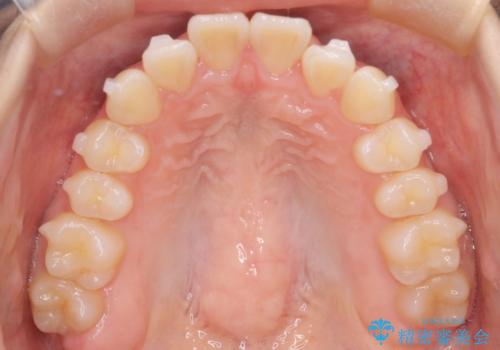

- 前歯が出ていることを主訴に来院されました。

下顎前歯が1本欠損していることもあり、前突はある程度残ることを説明し、インビザラインにて治療を行いました。

今回は抜歯矯正ではなく歯列弓の拡大とIPR、遠心移動を行って配列することができました。

口元も改善し患者さんには喜んでいただけました。